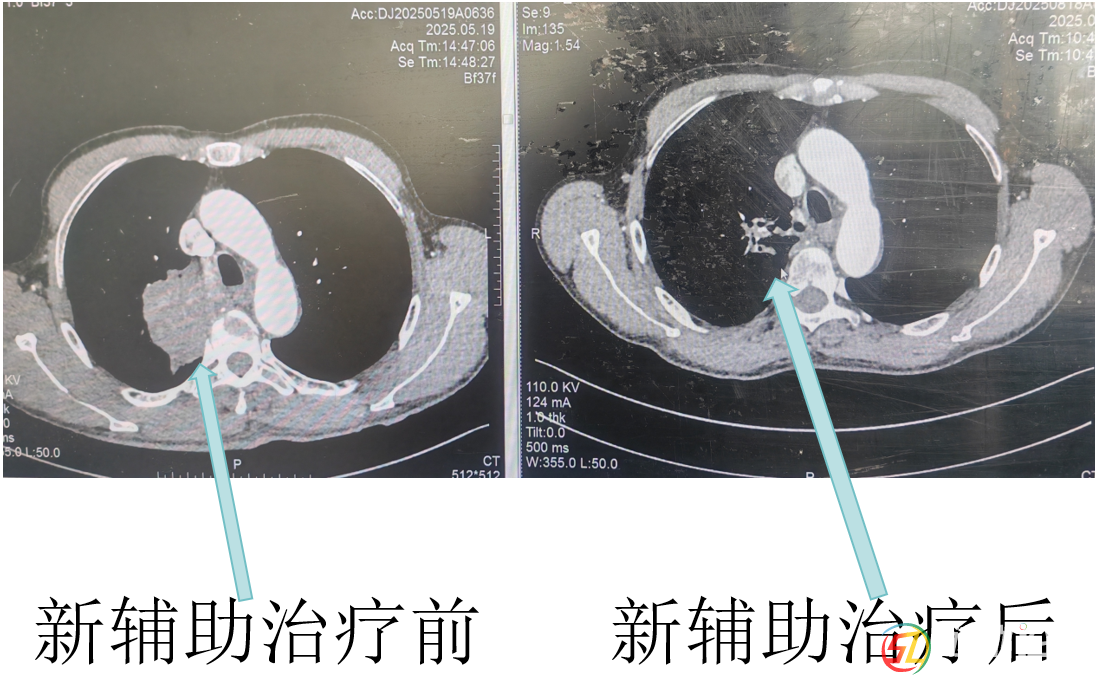

經(jīng)呼吸與危重癥醫(yī)學(xué)科醫(yī)生杜鵑三個(gè)周期的藥物治療后,復(fù)查CT顯示羅大爺肺上的腫瘤明顯縮小了!彭均偉判斷,現(xiàn)在手術(shù)有望完整切除腫瘤。就在大家看到希望時(shí),新的問題出現(xiàn)了。羅大爺有幾十年的老慢支和哮喘病史,肺功能檢查結(jié)果很差,根本達(dá)不到肺葉切除的手術(shù)標(biāo)準(zhǔn)。而且他三年前還因?yàn)樾呐K病做過冠脈支架手術(shù),長期服用阿司匹林,這又增加了手術(shù)出血風(fēng)險(xiǎn)。面對這些困難,彭均偉先為羅大爺制定了詳細(xì)的肺功能康復(fù)計(jì)劃,經(jīng)過一段時(shí)間的精心調(diào)理,羅大爺?shù)姆喂δ芙K于提升到了可以接受手術(shù)的水平。